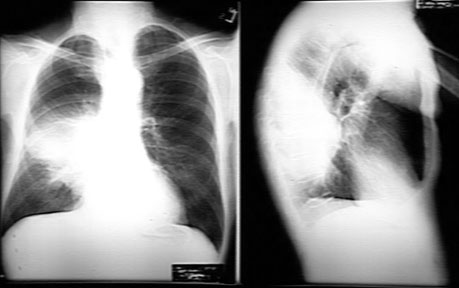

CXR Case 1: Density in the projection of right mid lung field silhouetting with right heart margin suggesting RML disease. Note also right hilar fullness.

CXR Lateral: Consolidation in the projection of RML.